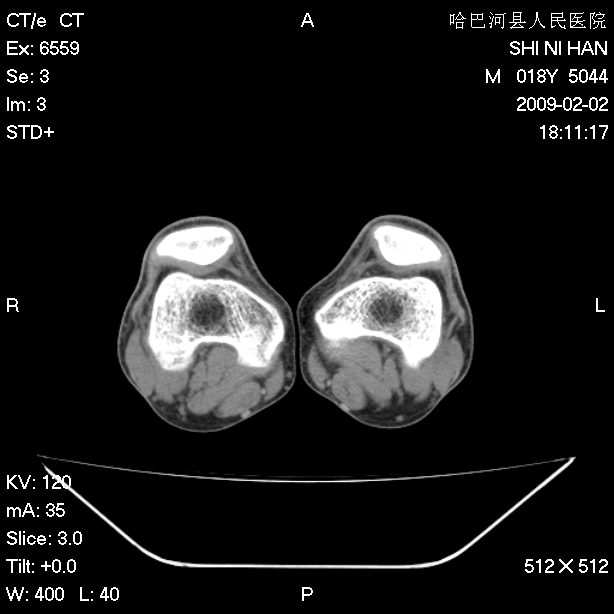

标题: CT17889:外伤后右膝关节反复疼痛3年余 [打印本页]

标题: CT17889:外伤后右膝关节反复疼痛3年余

ct未见明显异常。关节腔未见明显积液,半月板未见明显撕裂。但最好还是mri看看韧带及半月板情况。